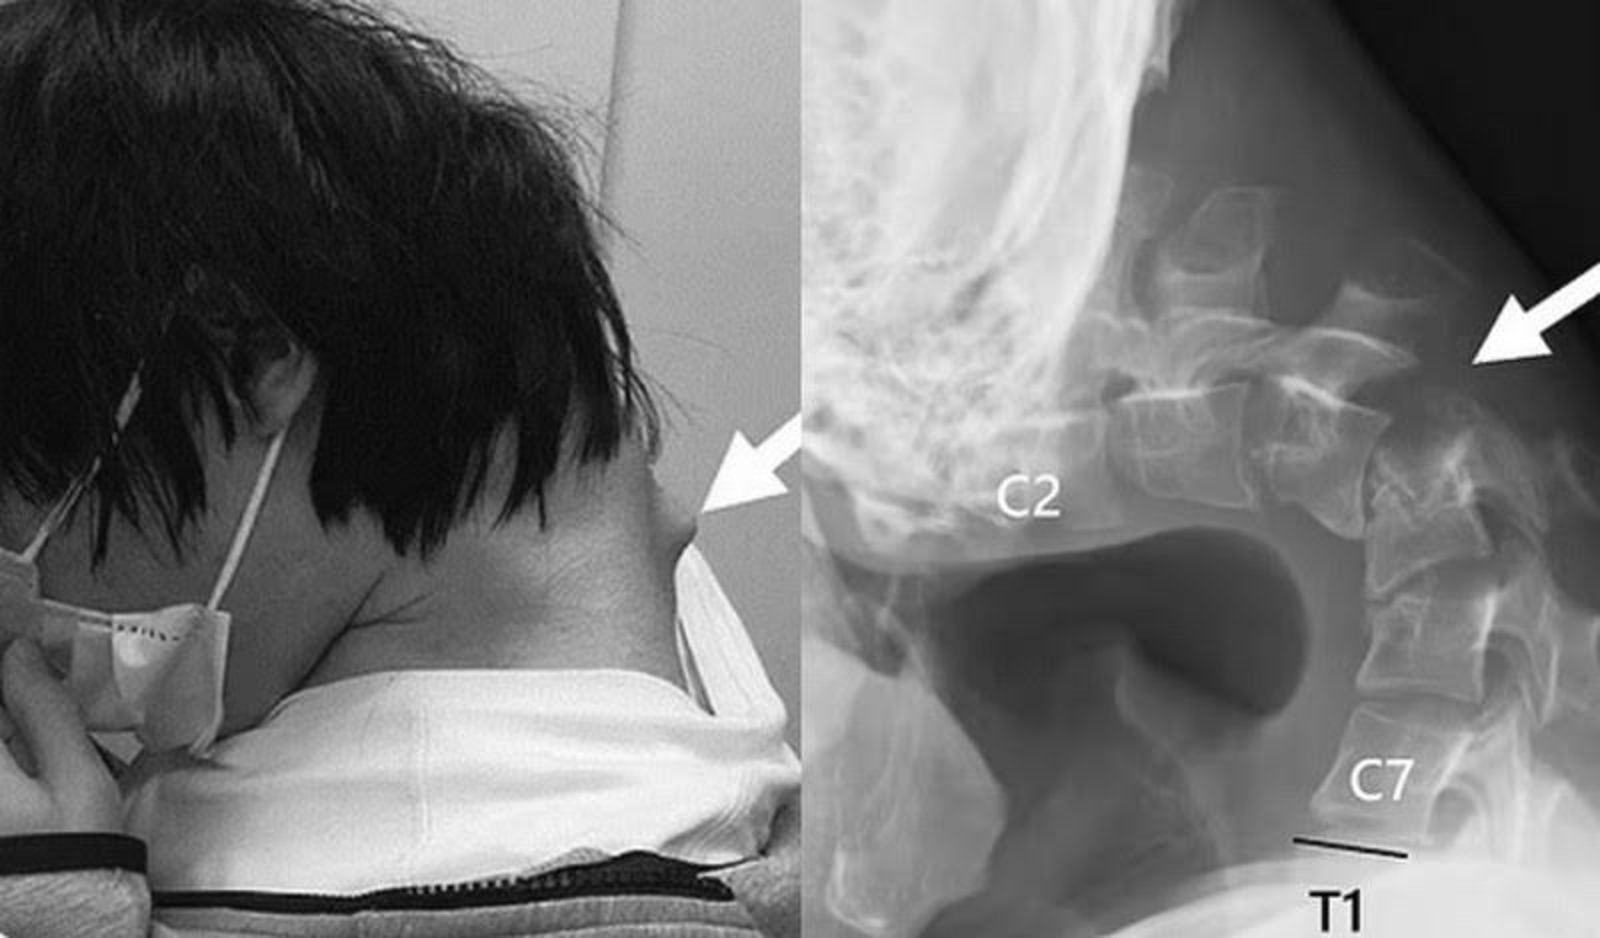

醫療團隊表示,該名男子青少年時期慘遭霸凌,使他封閉自己,輟學後常年躲在房間裡沉迷於手機遊戲,長時間低頭玩遊戲,逐漸與社會隔絕。醫療團隊進行影像檢查後發現,該名男子的頸椎出現變形和位移,甚至長了一個腫塊,確診罹患「頭部下垂症候群」(Dropped Head Syndrome)。醫師判斷,這是因為他的椎骨處於不自然的位置,導致「過度伸展」所致。

醫療團隊考量患者配戴護頸不適,調整治療方案改以手術治療,移除變形的頸椎骨和疤痕組織,並植入金屬螺絲與鋼釘固定骨架。術後半年,這名男子頭部已恢復正常位置,抬頭和吞嚥功能也日漸改善。醫師趁機呼籲大眾,使用智慧型手機務必留意使用時間和姿勢,年輕族群尤須注意。